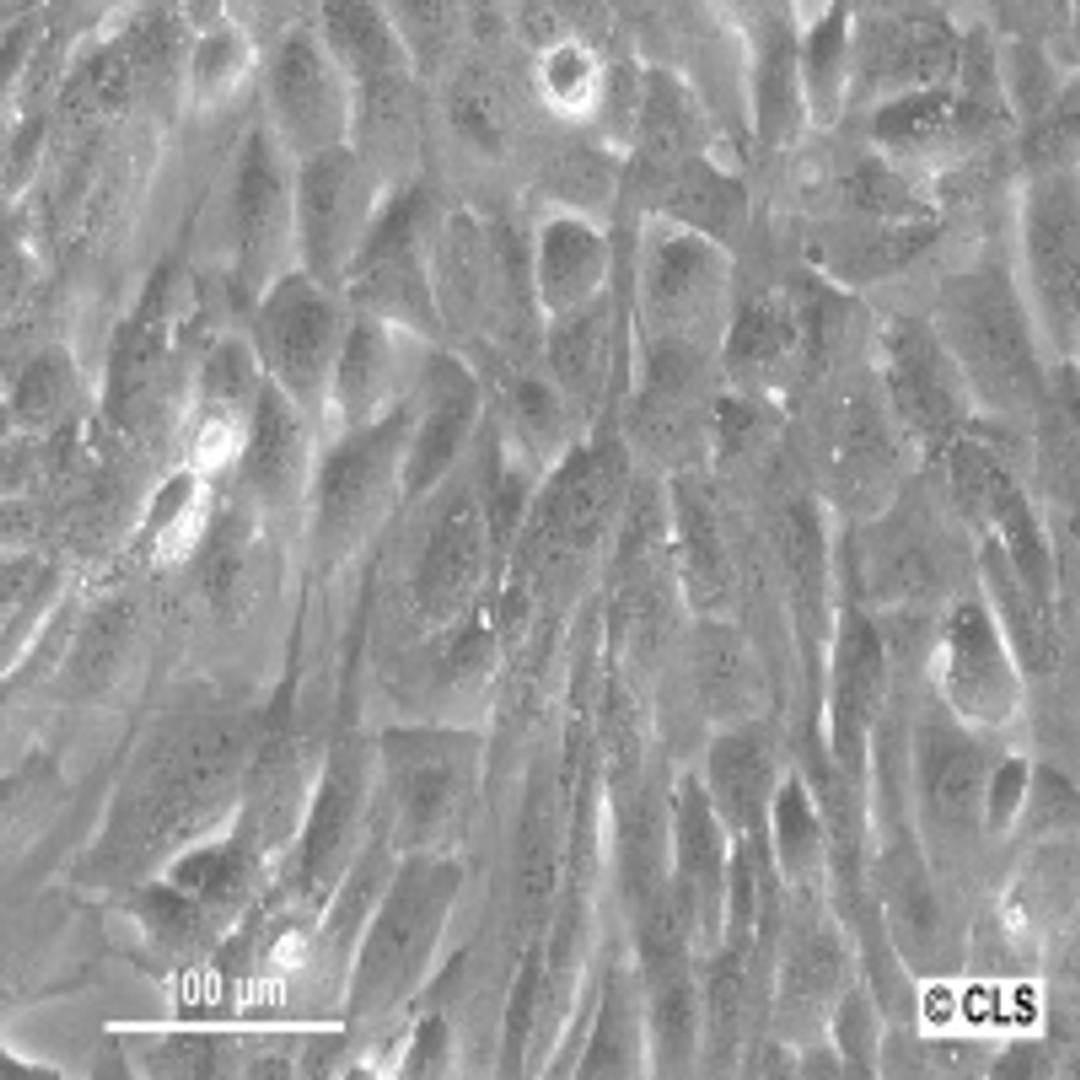

Human Bone chondrosarcoma cell line SW-1353

Morphology: Fibroblast

Growth Properties: Monolayer, adherent